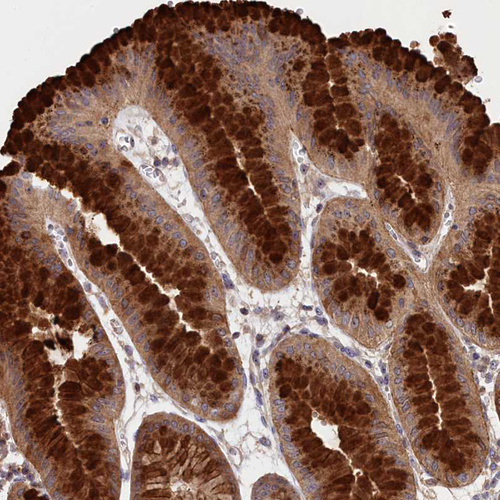

Immunohistochemical staining of human stomach shows strong cytoplasmic positivity in glandular cells.